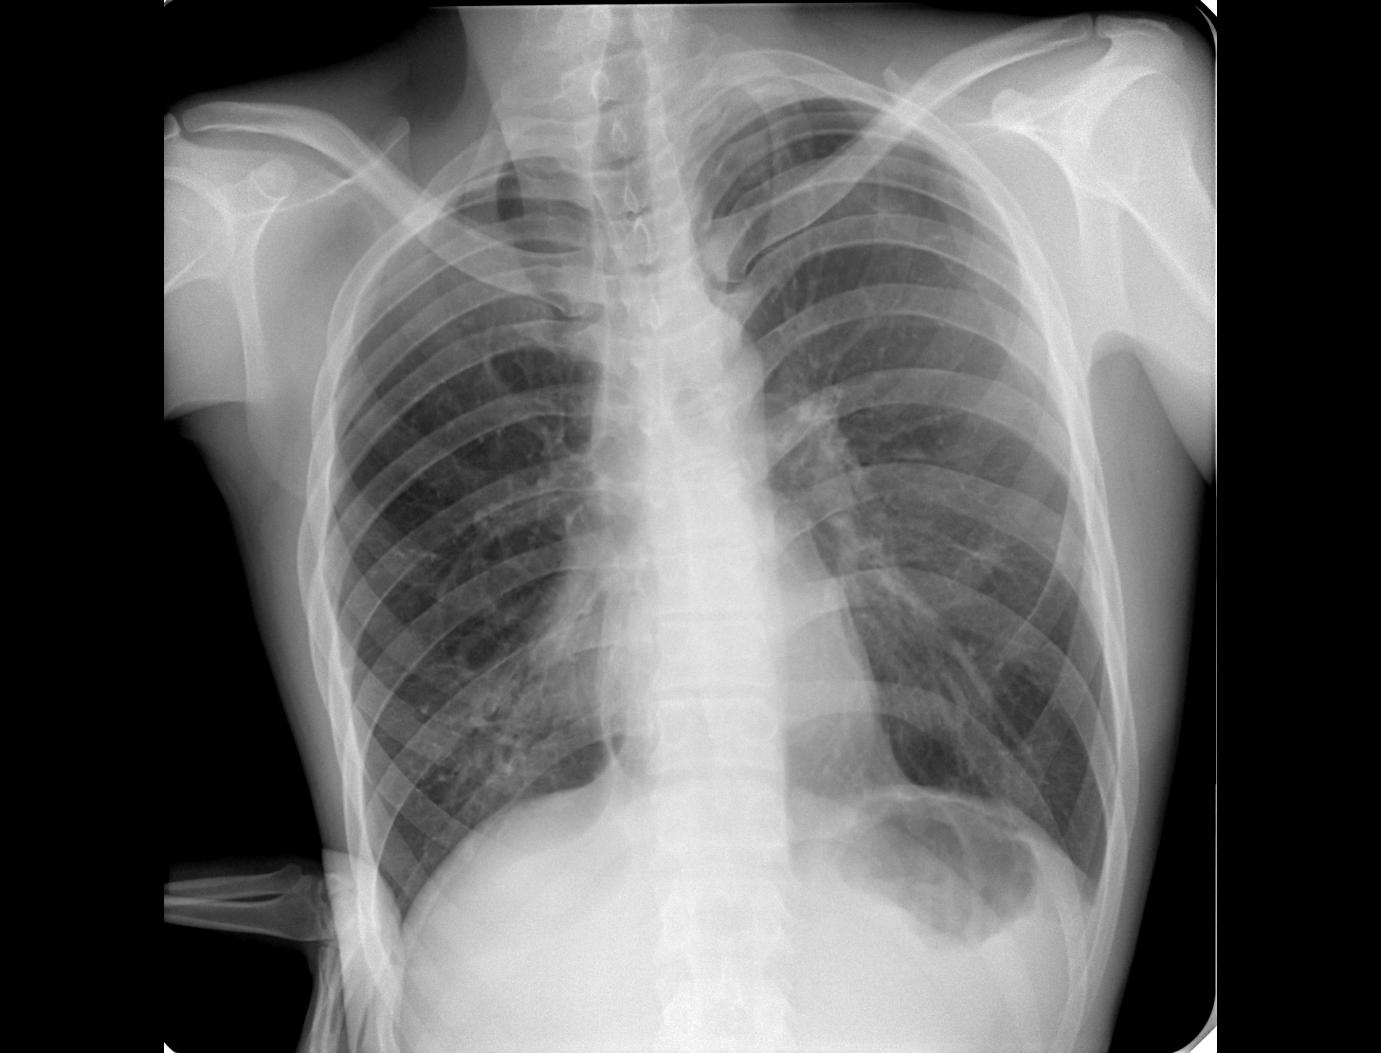

Медицина и диагностика: Аномалии ребер на рентгене